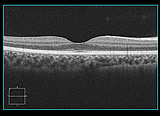

光干渉断層計(OCT)

- 光干渉断層計(OCT)は、網膜(カメラで例えるとフィルムにあたる部分)の断層画像を撮影します。主に、加齢黄斑変性症、糖尿病黄斑症、黄斑円孔、網膜剥離、黄斑上膜、緑内障などの疾患を精密検査するために行います。

- これまでの眼底検査では行えなかった目の奥にある網膜の立体的な情報を得ることができます。

網膜の断層像